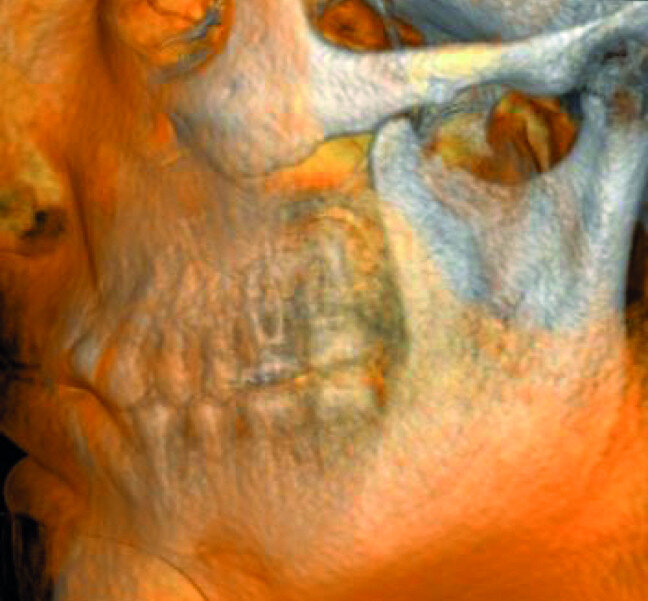

A patient was referred to the office with problems related to separated files. He was a pilot and was complaining of pus draining from his nose when flying. From the preoperative radiograph (Fig. 1), it was clear that there were two separated file fragments in the mesial canals and one cone passing beyond the apex in the palatal root. I requested an iCAT scan, and from this, the left sinus was clearly almost full with inflammatory fluid (Fig. 2) and the cone in the palatal canal was clearly emerging into the sinus. We could also see the two separated files in the two mesial canals clearly in the MPR view (Figs. 3 & 4), as well as another file entering the sinus and not attached to the canal (Fig. 5). We could see the file using different filters (Figs. 6–9), as well as the inflammation inside the sinus and the separated file. We additionally gained a better idea of the location of the cone protruding from the palatal canal into the sinus.

The treatment plan was to try to solve it with a conventional approach and if necessary to perform microsurgery to save the tooth. With the help of H-files, I managed to retrieve the cone from the palatal root, but the files inside the mesial root were impossible to bypass or even to reach with ultrasonic tips. I decided not to overdo it in order to avoid creating an additional problem, like perforating the canal, and decided to seal the canals (Fig. 10). A surgical approach was immediately taken for the mesial canals, cutting 3 mm of the mesial root using the Impact Air handpiece (SybronEndo), and this gave me a direct view of the Schneiderian membrane, where the third file was barely hanging (Figs. 11 & 12). I managed to delicate grab it and to remove it (Fig. 13). Figure 14 shows the postoperative situation, after performing retrograde preparation of the mesial canals.